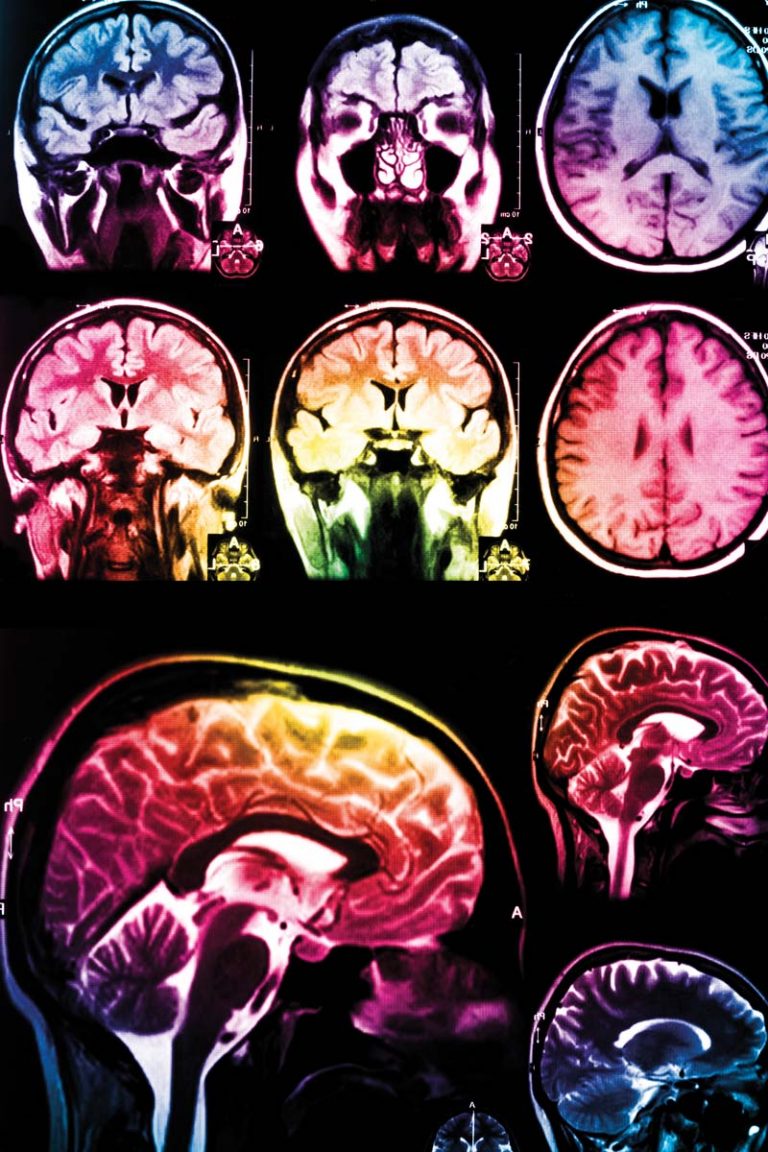

Инсульт, или острое нарушение мозгового кровообращения, – это нарушение неврологической активности со стороны сосудистого генеза. Оно проявляется остро или относительно остро с появлением очаговой неврологической симптоматики.

Другими словами, инсульт – это поражение головного мозга, возникающее в результате сосудистого конфликта, нарушения мозгового кровообращения. Проще говоря– инсульт является результатом поражения сосудов головного мозга. По патогенетическому механизму инсульты подразделяют на ишемический и геморрагический.

Ишемические инсульты, или инфаркты мозга, возникают в результате нарушения кровоснабжения мозга из-за закупорки сосудов. Часто это происходит по причине атеросклеротических изменений.

Причиной острого нарушения мозгового кровообращения по геморрагическому типу служит разрыв сосудов, крупных и мелких, или нарушение их проницаемости, в результате чего кровь пропитывает вещество головного мозга. Тяжесть заболевания классифицируется, исходя из калибра сосуда и его местонахождения.